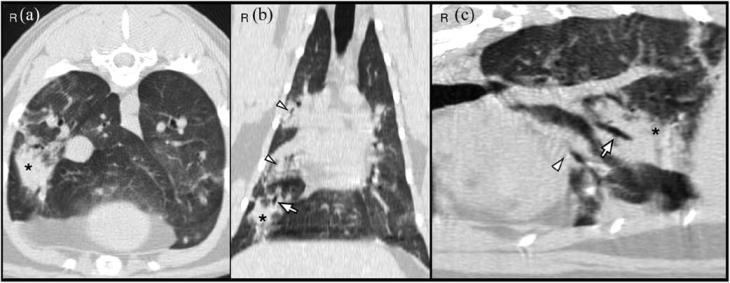

The CT images showed a monostotic, diaphyseal, fusiform, expansile, highly lytic mass involving the cortex of the ulna, sparing only the medial aspect and measuring 42 × 11 × 9 mm (Figure 2). There was no evidence of sequestrum formation. There was moderate ground-glass opacity and mild bronchial wall thickening affecting the right middle, right caudal, right accessory and left caudal pulmonary lobes. There were four areas of hyperdense alveolar filling observed in the right pulmonary lobes (Figure 3). These areas were fairly well defined and highly attenuating; they were localised to the dorsal and middle aspect of the right caudal lobe, ventral aspect of the right middle lobe and caudal portion of the right cranial lobe. Some of the bronchi involved in these areas of consolidation were truncated. No lymphadenomegaly was evident. Differentials for the pulmonary findings were multifocal infectious disease, haemorrhage and pulmonary metastatic disease (less likely). Atelectasis was ruled out because the areas of hyperattenuation were in a non-dependent position, and both lungs were optimally inflated and symmetrically expanded.

Figure 3 (a) Transverse, (b) dorsal and (c) lesion-orientated oblique sagittal multiplanar CT reformatted images of the thorax. A focal area of pulmonary consolidation is visualised in the right caudal lobe (*). There is a truncated bronchus within the lesion (arrow). Other areas of pulmonary hyperattenuation can be seen on the right cranial and right middle pulmonary lobes (arrowheads)